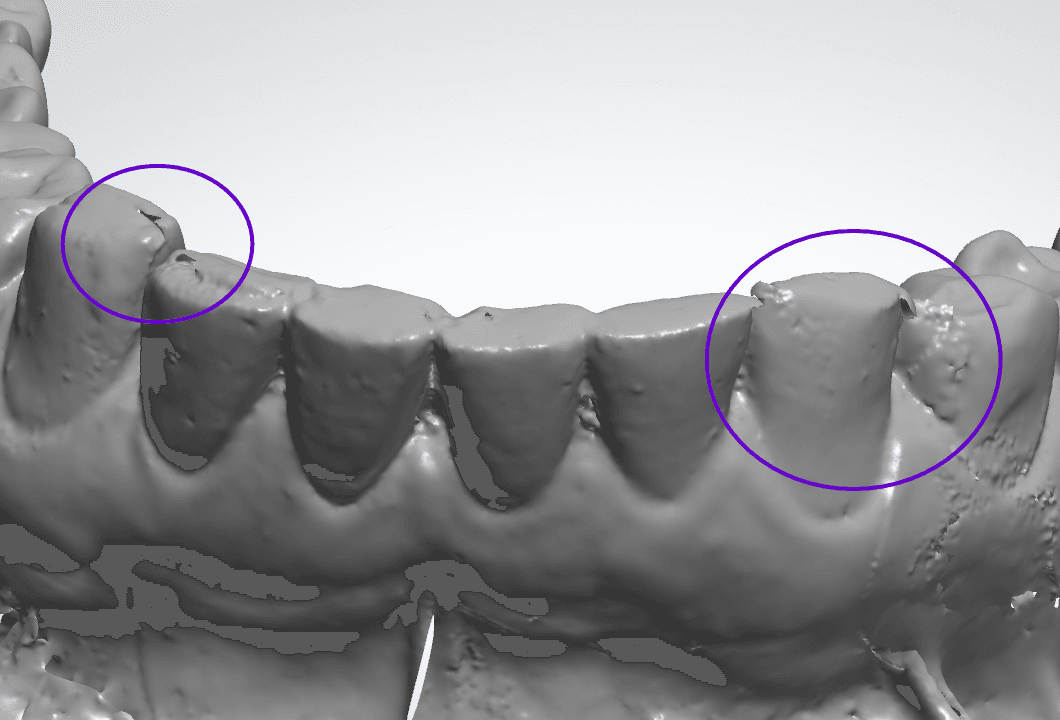

Falha de “Costura”

O escaner funciona tirando varias fotos da boca e vai “costurando” uma com a outra, formando uma imagem 3D, como se estivesse tecendo uma malha de tecido, tanto que é muito comum usar o termo “Malha” para se referir a um escaneamento 3D.

É muito comum você ter um defeito nessa junção da malha vestibular e lingual nas incisais Bateria Labial (tanto superior quanto inferior), esse defeito também conhecido como “falha de costura”.

Apesar de parecer um defeito pequeno ele pode prejudicar a adaptação do alinhador fatalmente por um lado da boca não ter alinhamento com o outro.